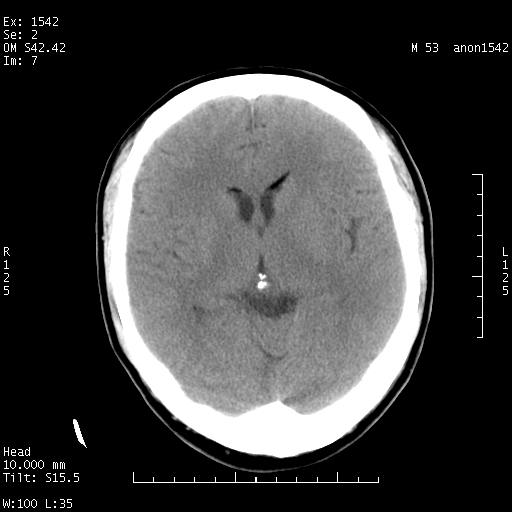

左侧鞍旁不规则低密度,此区域和侧脑室有液平。若无外伤史。考虑左侧鞍旁表皮样囊肿自发破溃。

1 囊性肿物. 2 请楼主上传介少病人资料. 3 表皮样囊肿或胆脂瘤都在考虑范围内,确切的不知ct值是多少.4了解病史后在缺定.

左侧鞍旁表皮样囊肿自发破溃

考虑:左侧鞍旁表皮样囊肿自发破溃,是否合并感染?